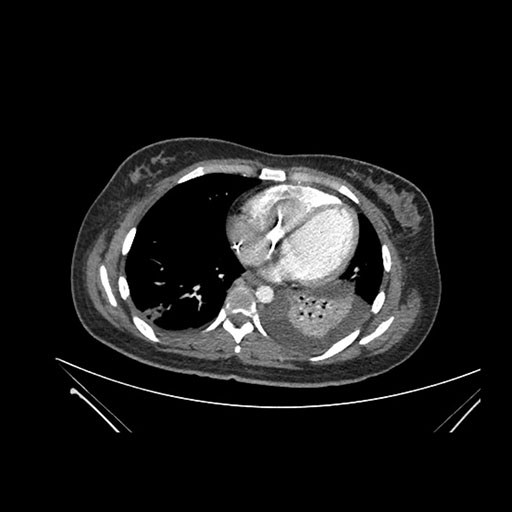

Imaging Analysis

Look through the patient's CT scan to identify any areas of concern for the necessary procedure.

Axial Arterial